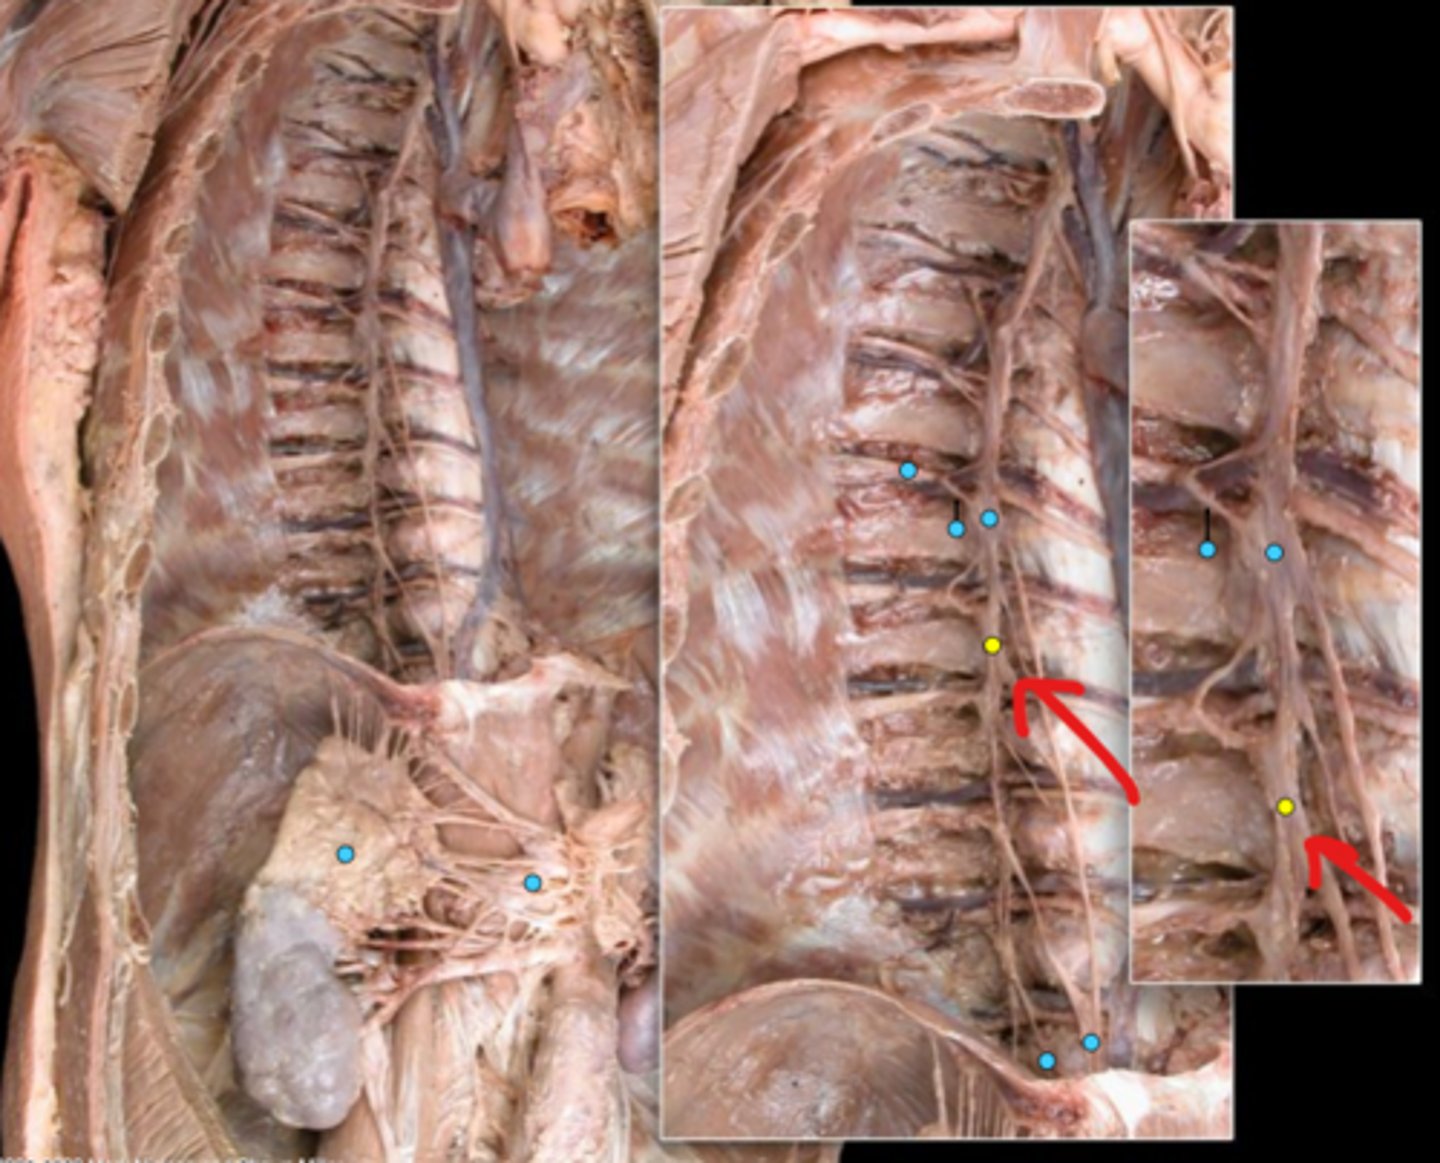

Suprarenal gland

Celiac ganglion

Intercostal nerve

Communicating ramus

Sympathetic trunk ganglion

Sympathetic trunk

Lesser splanchnic nerves

Greater splanchnic nerve

Anterior (ventral) ramus

Spinal nerve trunk

Posterior (dorsal) ramus

Spinal ganglion